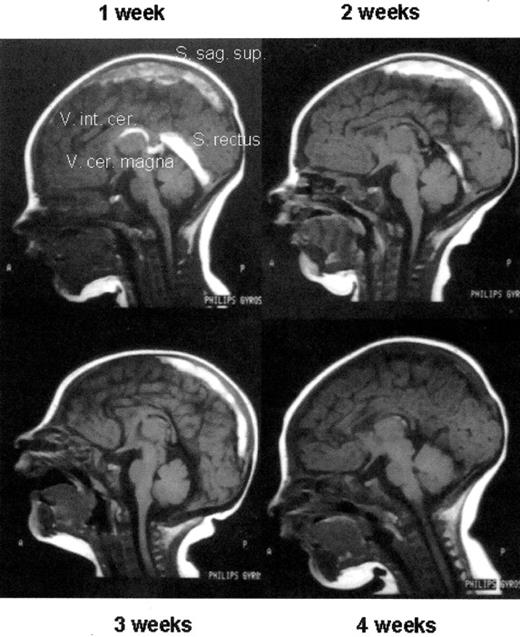

Thrombolytic therapy of an extensive sinus venous thrombosis in a newborn with heterozygous protein C deficiency by protein C concentrate after 1 week of ineffective UFH therapy (1 week) and, after initiating protein C replacement, at week 2, 3, and 4 of therapy, respectively. Note the almost complete re-canalization.